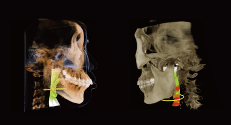

3D Fine Reconstruction

Minimum Tamaño de vóxel to 0.05 mm.

TMJ Diagnosis

SmartV-ENT has a visual pattern of comparison of left and right joints, allowing doctors to evaluate the diagnosis and treatment effect of temporomandibular joint diseases.